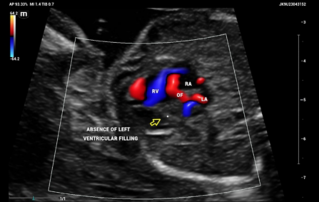

Ultrasound Journal 34 - Use of IOTA-ADNEX & O-RADS risk assessment models in MDT management of Adult Granulosa Cell Tumor

Comprehensive overview of granulosa theca cell tumors of the ovary, covering epidemiology, clinical presentation, diagnosis, treatment options, and prognosis for both adult and juvenile types.